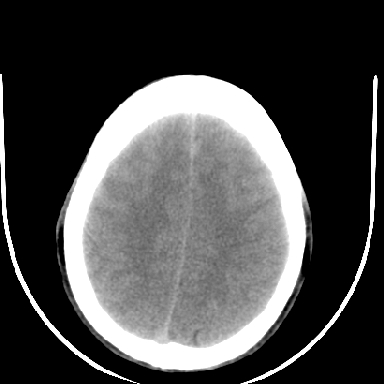

标题: CT6056:脑出血(血管畸形?) [打印本页]

标题: CT6056:脑出血(血管畸形?)

m 40突发头痛左侧偏瘫3小时

考虑高血压性脑出血,依据:

1是高血压性脑出血的好发部位,形态呈肾形,是高血压性脑出血的常见形状

2增强时占位效应加重了,考虑出血还没有停止

3病灶周围水肿不是太厉害,一般肿瘤出血水肿多非常明显

4病灶周围的‘软组织’影没有明显的强化

5至于脑血管畸形引起的出血,暂时没有看到明显的畸形血管影,也不太支持

支持右侧基底节脑出血

右侧基底节区脑出血.

支持右侧基底节区(主要为外囊区)原发性脑出血。

另附部分资料:“血液溢出血管外形成血肿,其内含有大量血红蛋白、血浆白蛋白,球蛋白,因这些蛋白对x线的吸收系数高于脑质,故ct呈现高密度阴影,ct值达40~90h,最初高密度灶呈非均匀一致性,中心密度更高,新鲜出血灶边缘不清。基底节区血肿多为“肾”型,内侧凹陷,外侧膨隆,因外侧裂阻力较小,故向外凸,其它部位血肿多呈尖圆形或不规则形”

术中抽出40ml陈旧血液,血肿底部似见一条索血管影